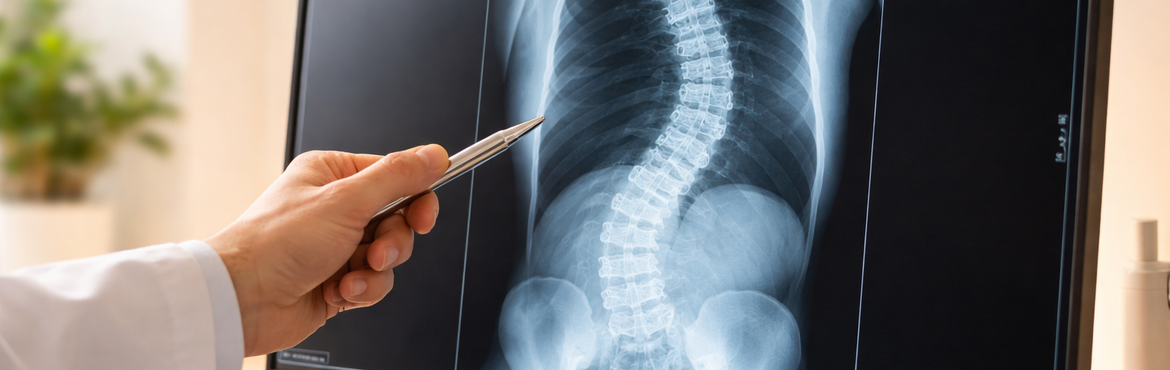

2. Bildgebung: Die wichtigste Untersuchung ist das Röntgen der gesamten Wirbelsäule im Stehen. Anhand dieser Bilder kann der Arzt den sogenannten Cobb-Winkel messen. Dieser Winkel gibt in Grad an, wie stark die Wirbelsäule verkrümmt ist, und ist maßgeblich für die Wahl der Therapie. Bei Bedarf (z. B. vor Operationen oder bei Verdacht auf Nerveneinengungen) werden zusätzlich eine Magnetresonanztomographie (MRT) oder Computertomographie (CT) durchgeführt.